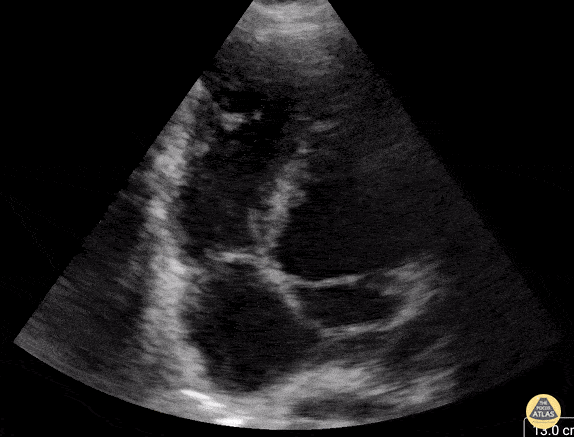

Truncus arteriosus, with the left pulmonary artery arising off the ascending aorta and the right pulmonary artery arising off of the descending aorta, right aortic arch, bilateral superior vena cava without bridging vein. Contributor: Callie Alt, MD, Nicklaus Children's Hospital